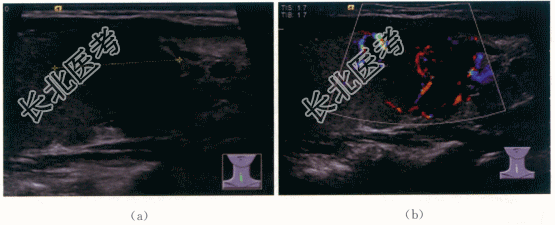

二、影像资料及诊断

1.影像资料

亚急性甲状腺炎。